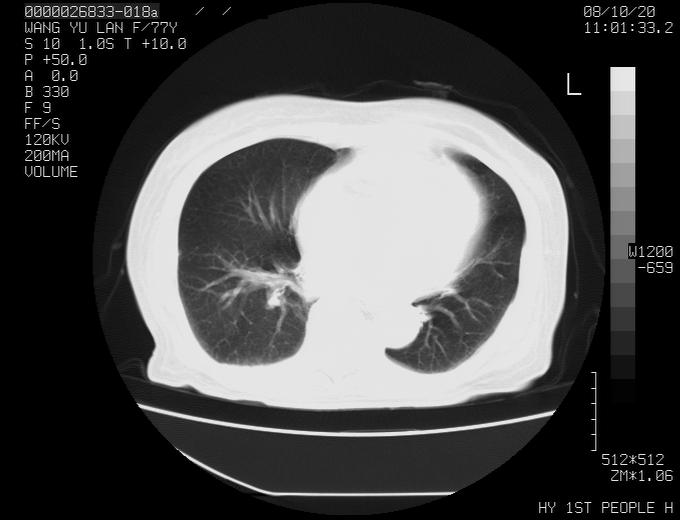

女性,77岁,胸部疼痛半月。左上肺团块影,本人考虑血管畸形,请分析

非常典型的avm(谢谢楼主,收藏了)

左上叶前段多发结节肿块并前段支气管息肉样结节、上叶腋亚段阻塞性肺炎,以结核可能性大。

1、考虑avm可能性大。2、纵隔有肿大淋巴结,左肺上叶有炎性病变,不排除肺癌并转移可能。